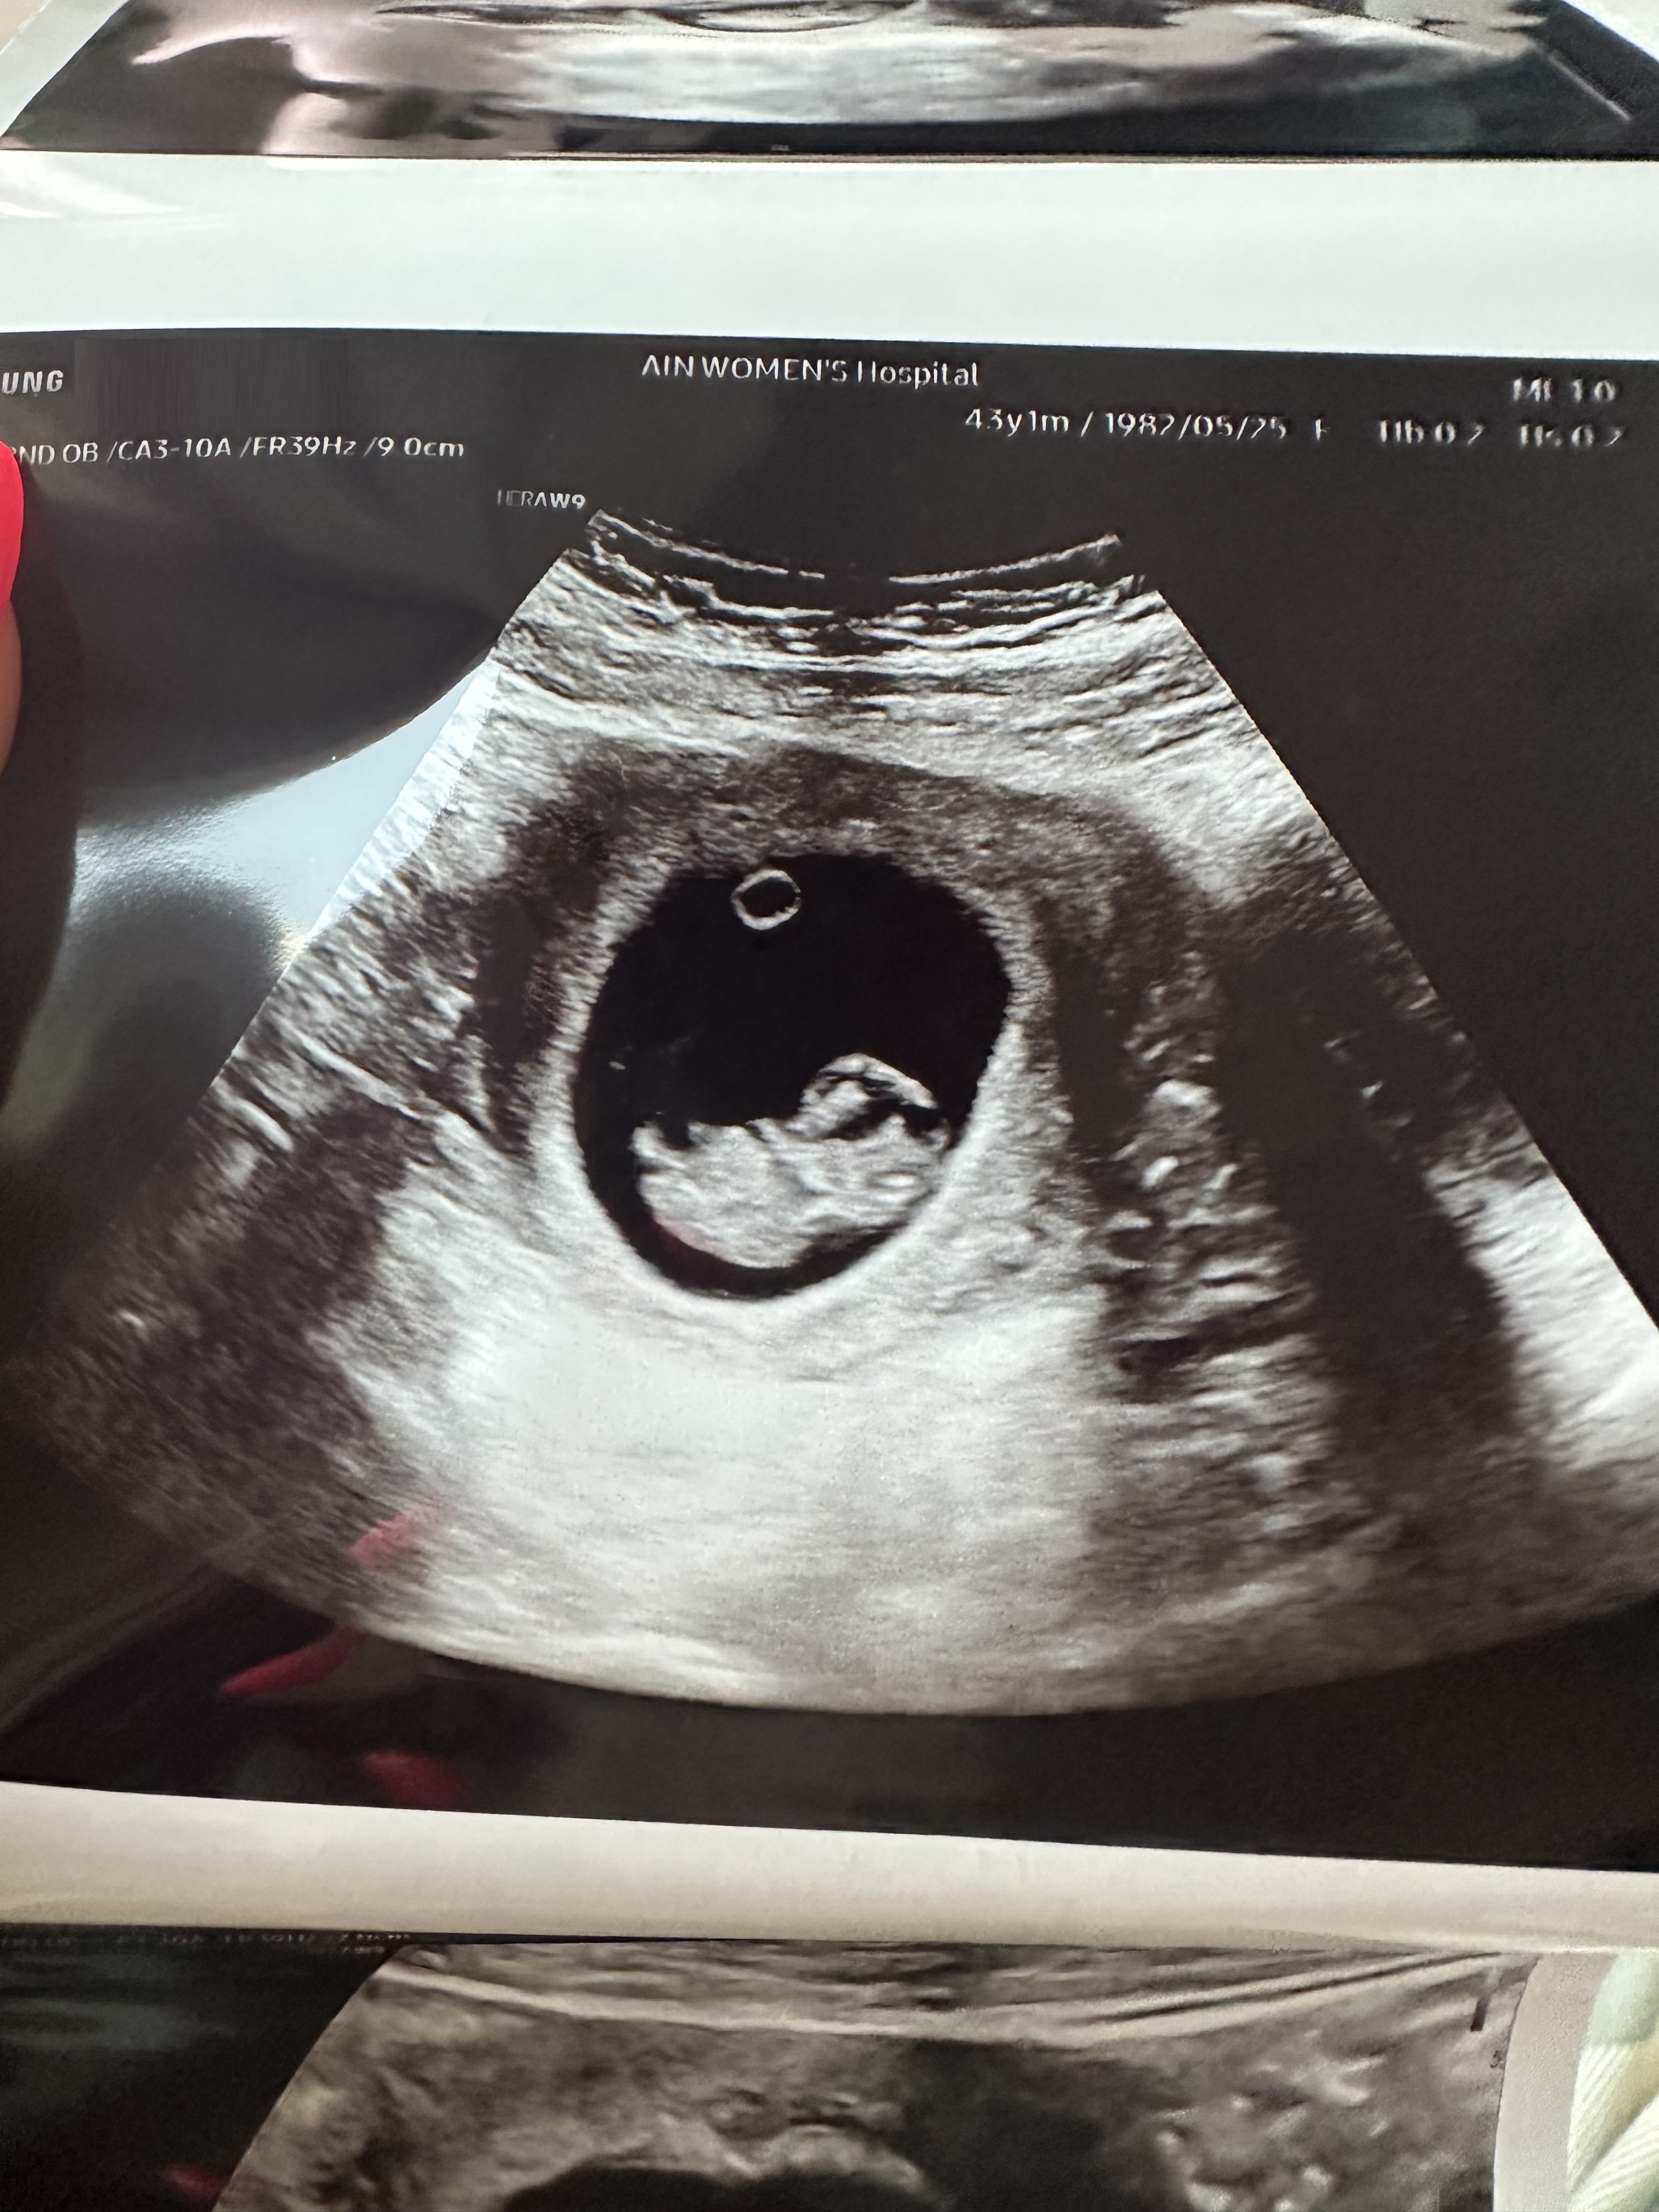

| 가슴 떨리는 임신 이야기를 공유해 주세요. | 나이도 있고 잦은 반복 유산으로 지쳐 포기할까 고민도 많이 했습니다. 하지만 *“이번이 마지막이다”*라는 마음으로 PGT 검사를 진행했고, 마침내 이쁜 아기를 만날 수 있었습니다. 처음 결과를 확인했을 때는 믿기지 않아 눈물이 날 정도로 벅찼습니다. 아직 갈 길은 멀지만, 끝까지 잘 지켜서 건강하게 순산하고 싶습니다. |

| 치료 도중 느꼈던 가장 기뻤던 순간과 절망적인 것들은 무엇인가요? 잊지 못할 경험이 있나요? | PGT 과정에서 쉽지 않은 결과들이 반복되었지만, 이유정 원장님의 세심한 설명과 판단 덕분에 마지막까지 이어갈 수 있었고, 결국 건강한 임신을 확인할 수 있었습니다. 그리고 이식 후 초음파에서 아기의 심장 소리를 처음 들었을 때, 그 순간은 제 삶에서 가장 큰 기쁨이자 가슴 떨리는 경험이었습니다. 반대로 가장 절망적이었던 경험은 연달아 두 번의 계류유산을 같은 주수에서 겪었을 때였습니다. 모든 것이 무너지는 듯한 좌절감이 밀려왔지만, 포기하지 않고 다시 일어났기에 지금의 기적 같은 순간을 맞이할 수 있었다고 생각합니다. |